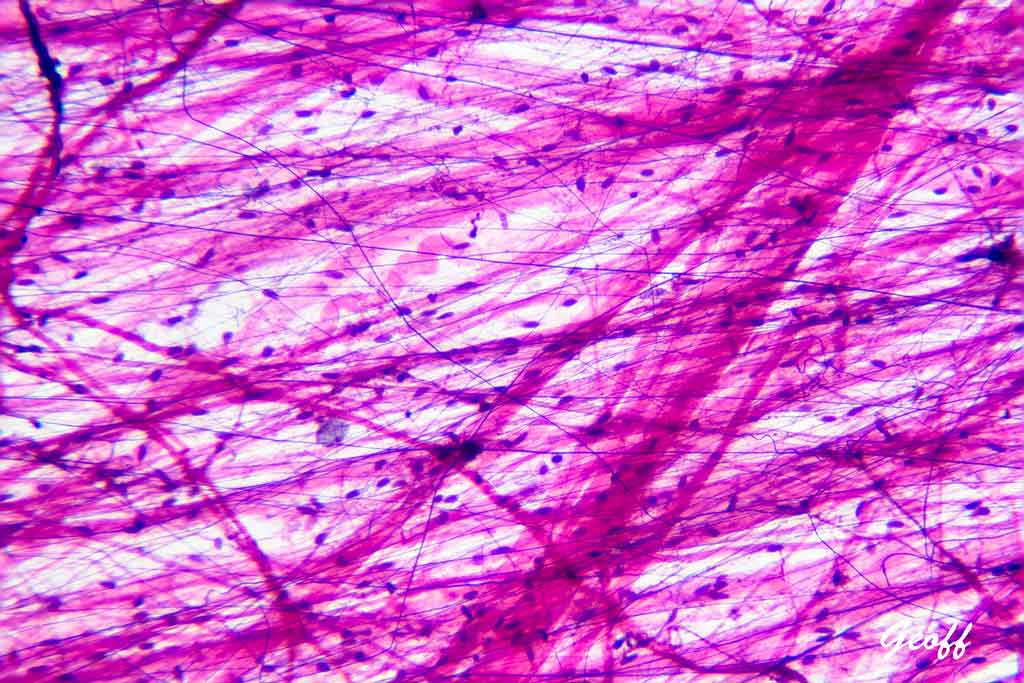

| Description | Liver t.s., Pancreas t.s., Intestine t.s., Lung t.s., Kidney t.s., Testis t.s., Appendix t.s., Oesophagus t.s., Thyroid gland t.s., Stomach t.s., Ovary t.s., Adrenal gland t.s., Kidney l.s., Spleen t.s., Caecum t.s., Rectum t.s., Blood smear, *, Squamous epithelium, Stratified squamous epithelium v.s., Columnar epithelium, Ciliated epithelium, Areolar tissue, Adipose tissue, Hyaline cartilage t.s, Bone ground thin t.s., Bone decalcified t.s., Striated muscle l.s., Cardiac muscle l.s., Non-striated muscle l.s., Nerve t.s., Ovary adult v.s., Artery t.s., Blood smear, Ileum t.s., Ovary with corpus luteum, Spinal cord t.s., Stomach cardiac t.s., Tooth decalcified, Brain cerebrum t.s., Bone calcified t.s., Duodenum t.s., Heart t.s., Jejunum t.s., Larynx t.s., Oviduct t.s., Skin v.s., Tongue t.s., Vein t.s., Brain cerebellum t.s., Epiglottis t.s., Heart l.s., Lung l.s., Lymph gland t.s., Parathyroid gland t.s., Salivary gland, Penis t.s., Stomach fundus t.s., Retina v.s., Tail t.s., Uterus t.s. |

Microscopes Prepared Slides

Mammalia Histology (Rat or Rabbit)